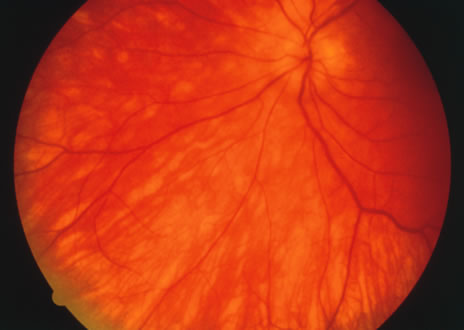

Fundus Findings.

Classically, there are broad areas of chorioretinal atrophy that may take a jigsaw pattern. Usually the atrophy is centered on the disc and spreads along the vascular arcades and then towards the fovea. Sometimes the choroiditis starts within the macula and spreads out from there. Both eyes tend to be affected although there may be marked asymmetry between the two eyes. The active disease appears as yellow-gray areas. If there is evidence of previous disease, then the active areas tend to be at the edge of the chorioretinal atrophy (Figs. 16 to 18). Rarely, there may be several noncontiguous areas of chorioretinal atrophy in the eyes. Retinal vasculitis at the site of an active lesion and retinal vein occlusions may rarely be seen.

Fig. 16. A. Color fundus photograph showing the jigsaw pattern of choroidal and retinal atrophy extending from the disc along the arcades. At the inferior edge of the superotemporal lesion there is a recurrence noted by the grayness of the retina. B. Fluorescein angiogram in the laminar venous phase showing a large window defect in the area of inactive choroiditis and blockage of the choroidal fluorescence in the area of active choroiditis. C. In the late phase of the fluorescein angiogram there is staining of the edges of the inactive choroiditis and marked hyperfluorescence in the area of active choroiditis.

Fig. 17. A. Classic inactive case of serpiginous choroiditis showing the jigsaw pattern of disease surrounding the fovea. B. Fluorescein angiogram showing staining of the edges of the inactive serpiginous choroiditis. There is blocked fluorescence in the areas of hyperplasia of the retinal pigment epithelium. C. Indocyanine green angiogram showing absence of fluorescence in the area of inactive choroiditis.

Fig. 18. Fundus photograph of active macular serpiginous. Because there is no previous evidence of scarring, it is difficult to distinguish by ophthalmoscopy alone from acute posterior multifocal placoid pigment epitheliopathy (APMPPE). The larger size and the age of the patient tend to help in distinguishing.